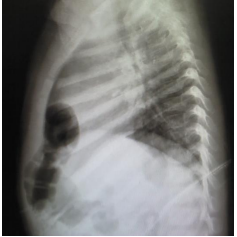

Menina de 1 ano apresenta tosse e coriza nasal hialina há 5 dias, sem febre. Exame físico: bom estado geral, frequência cardíaca de 120 bpm, frequência respiratória de 38 irpm, murmúrios vesiculares presentes e simétricos, com roncos transmitidos de vias aéreas superiores difusos. Antecedentes pessoais: 2 episódios de pneumonias tratadas ambulatorialmente, com 6 meses e 9 meses de idade. Raio x de tórax: imagens a seguir:

Enunciado 3405859-1